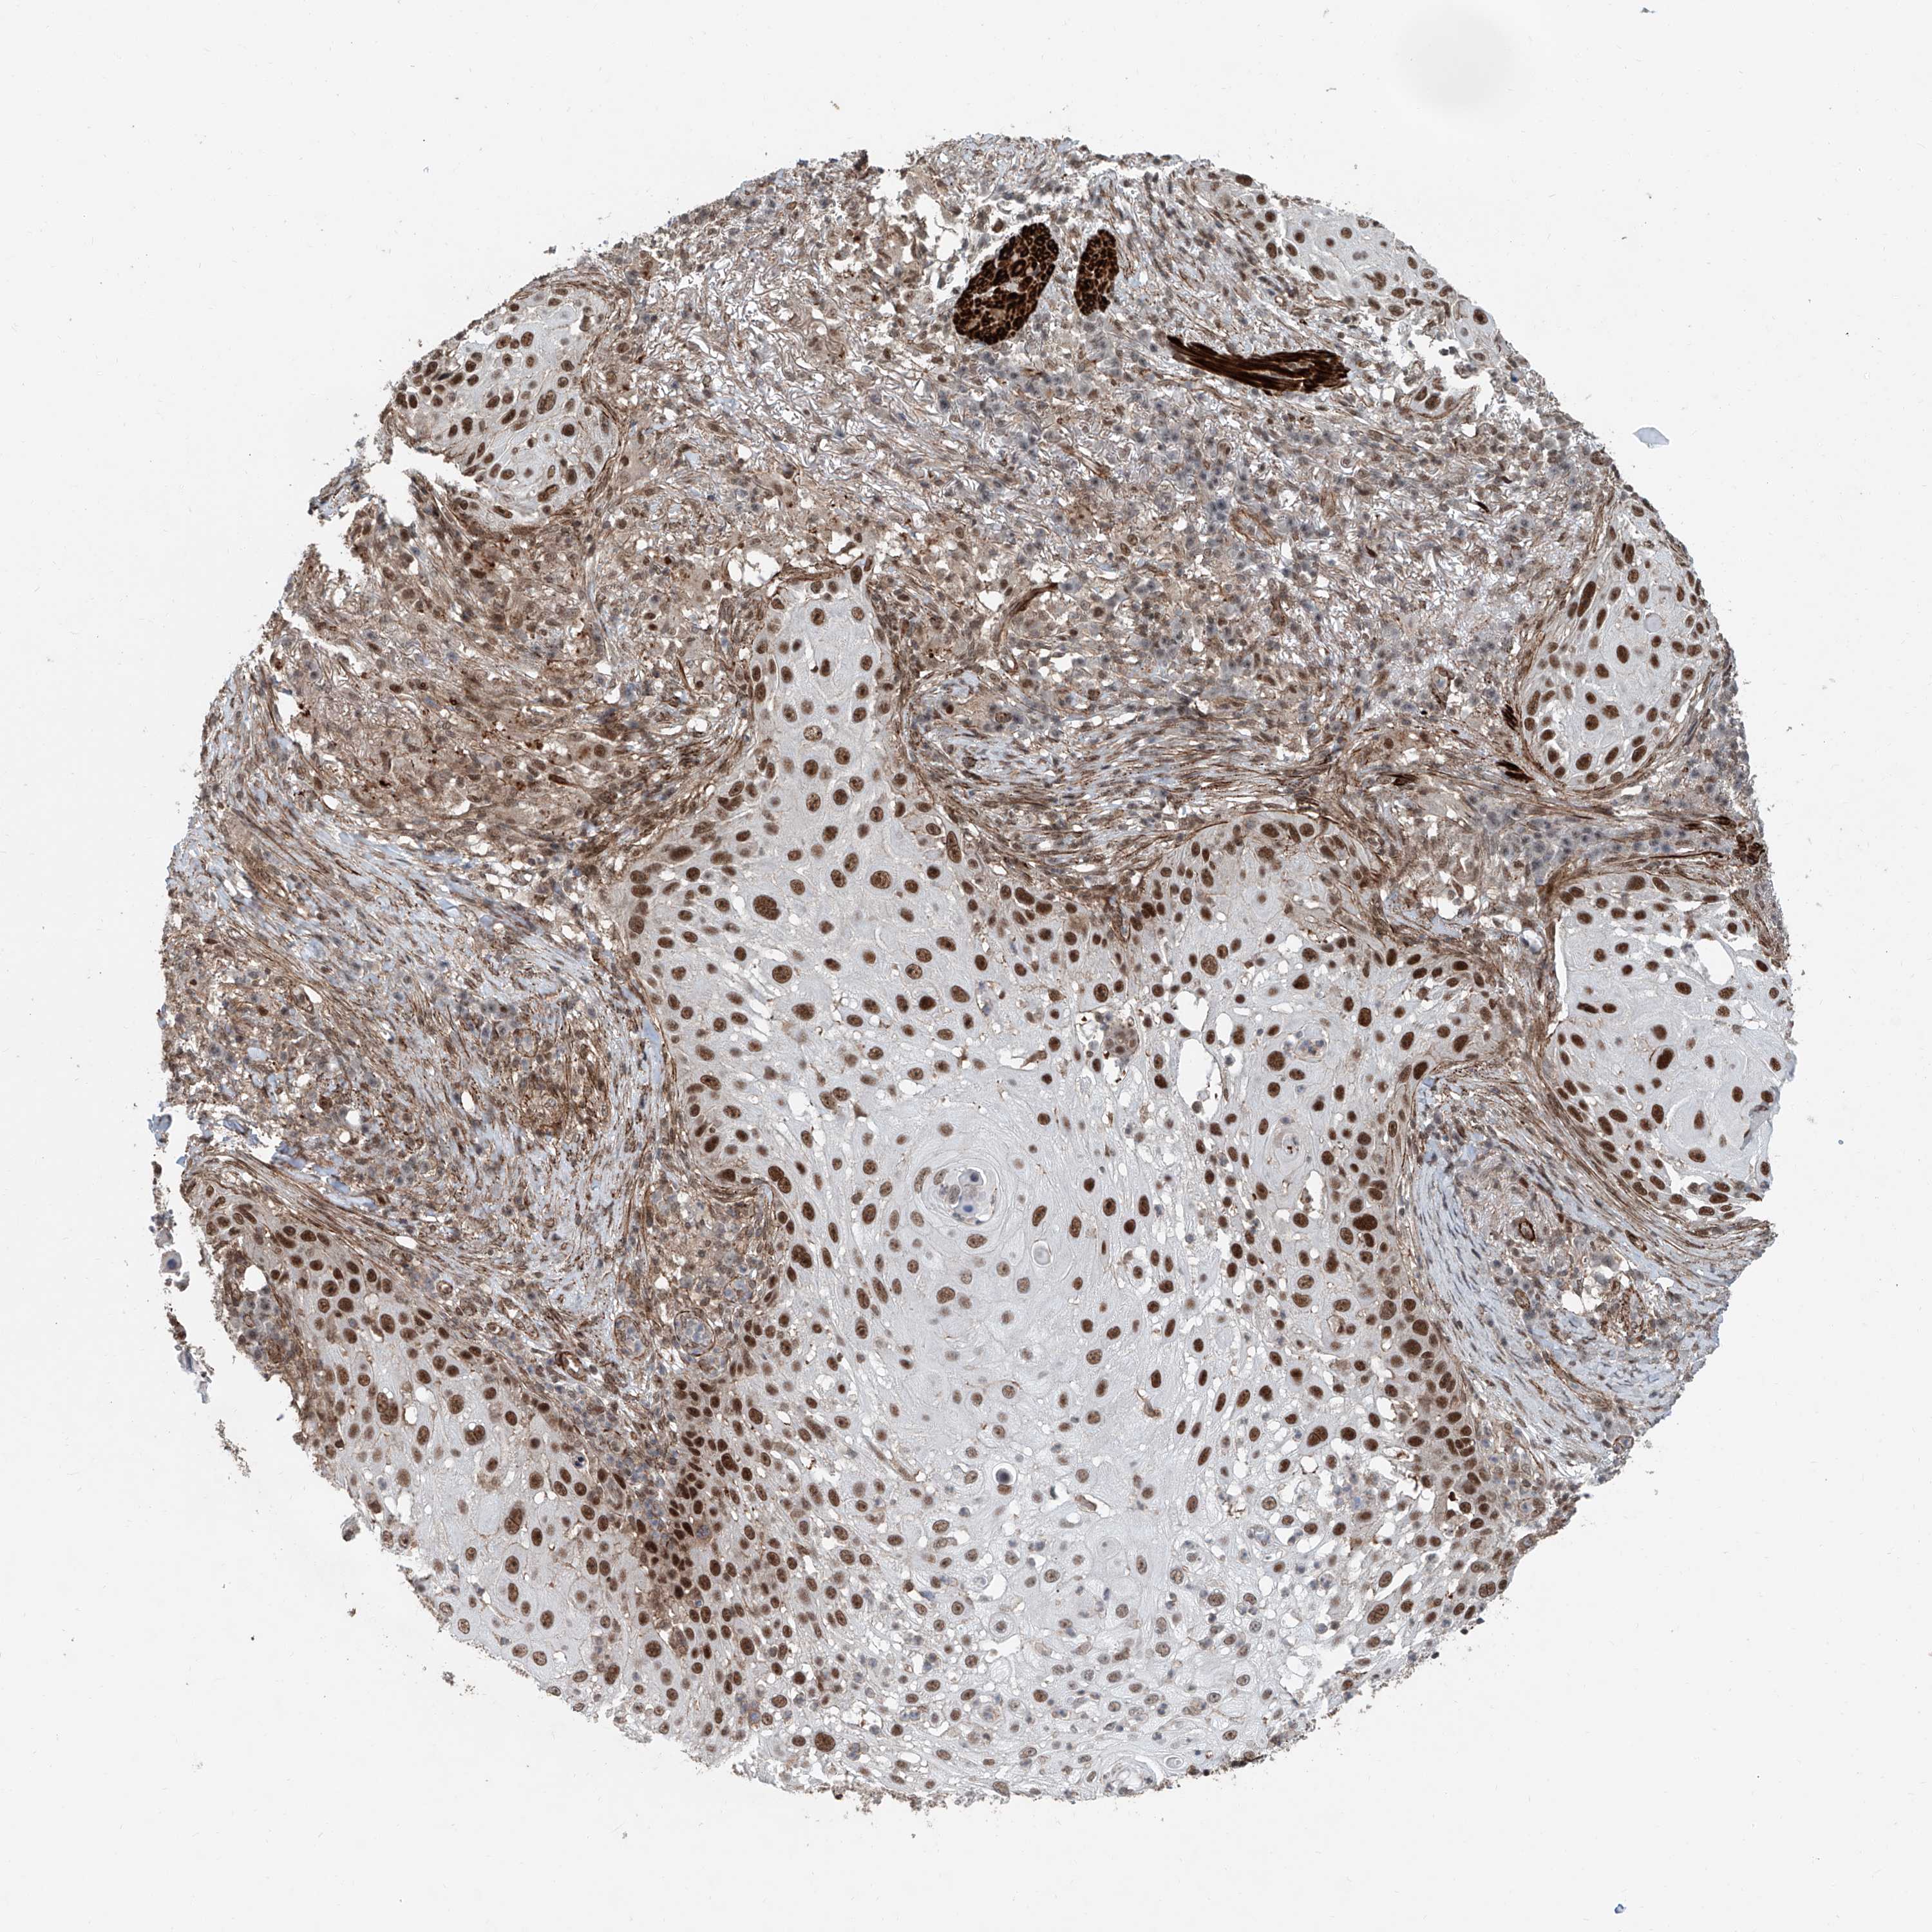

Basal cell and squamous cell cancer

SKIN CANCER - Protein expressioni

A mouse-over function shows sample information and annotation data. Click on an image to view it in a full screen mode. Samples can be filtered based on level of antibody staining by selecting one or several of the following categories: high, medium, low and not detected. The assay and annotation is described here.

Antibody stainingi

Antibody staining in the annotated cell types in the current human tissue is reported as not detected, low, medium, or high, based on conventional immunohistochemistry profiling in selected tissues. This score is based on the combination of the staining intensity and fraction of stained cells.

Each image is clickable and will lead to virtual microscopy that enables deeper exploration of all samples and also displays staining intensity scores, fraction scores and subcellular localization as well as patient and tissue information for each sample.

Antibody HPA028467

Staining

High

Medium

Low

Not detected

Intensity

Strong

Moderate

Weak

Negative

Quantity

>75%

75%-25%

<25%

None

Location

Nuclear

Cytoplasmic/membranous

Cytoplasmic/membranous,nuclear

Squamous cell carcinoma, NOS